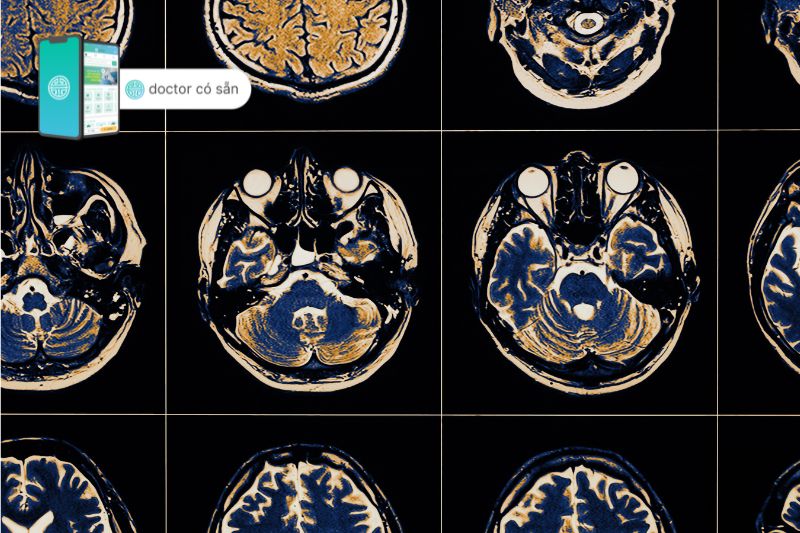

Chẩn đoán hình ảnh

Các nhà cung cấp dịch vụ chăm sóc sức khỏe thường sử dụng phương pháp chụp cắt lớp vi tính (CT), chụp cộng hưởng từ (MRI) và các xét nghiệm hình ảnh khác để loại trừ các vấn đề như đột quỵ, chấn thương não, khối u và những thay đổi khác đối với cấu trúc não của bạn.